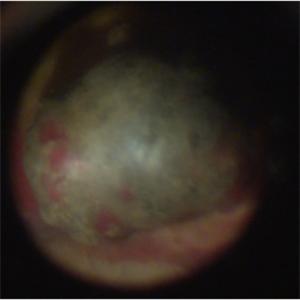

Melanoma-Fundus

Nov 12 2013 by Xuefeng Feng, MD, PhD

Fundus photograph of of a 52-year-old man with a choriod melanoma.

Condition/keywords: fundus photograph